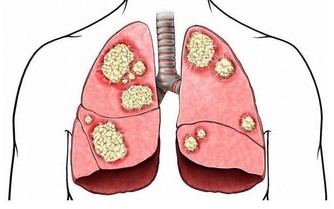

「悲傷」器官——肺

人們總是習慣用「多愁善感」來形容女生,認為「多愁善感」是天生的,是性格使然。其實,性格只是其中一個原因而已,還有一種可能是人的肺功能失調,肺不好的人總會有些悲傷和寂寞。只要肺的功能恢復正常,這種多愁善感、優柔寡斷的情緒就會消失。在飲食上,白色的食物對肺有益,可以多吃白蘿蔔、洋蔥、大白菜、山藥等,少吃辛辣的刺激性強的食物,這類食物入肺,對肺功能有不好的影響。